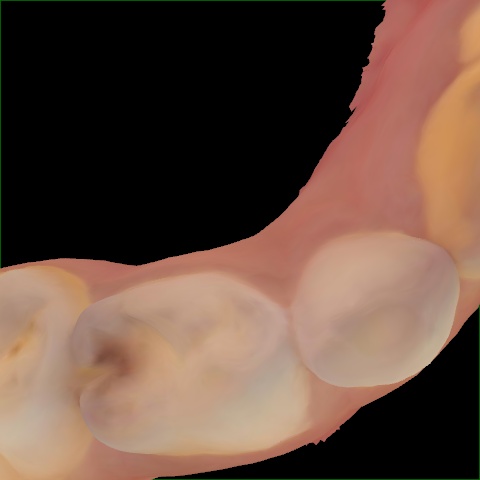

Incorrect Quality Level

The reference annotation for this image is

None

.

Please select the correct quality level.

Annotated as "Good"